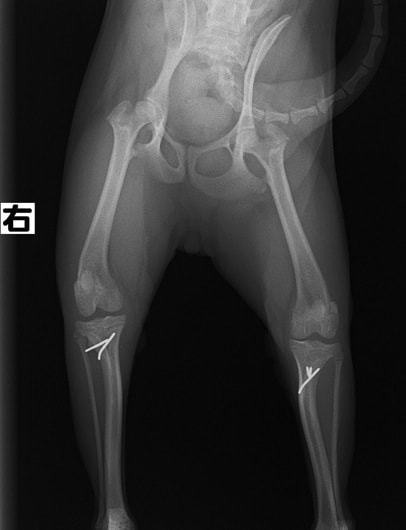

■ 症例22 ポメラニアン 1歳5か月 去勢雄

左後肢の挙上を主訴に来院した。整形学的検査、レントゲン検査より左右の膝蓋骨脱臼(左GradeⅡ〜Ⅲ、右Grade Ⅱ)を認めた。また、脛骨の前方引き出し試験の際に、引き出し兆候は認められないものの、疼痛が認められたため、前十字靭帯の損傷が疑われた。術中における、目視および関節内の操作によって、前十字靭帯の損傷や過伸展といった異常が認められなかったため、膝蓋骨脱臼の整復のみ実施した。手術手技は縫工筋及び内側広筋の解放、脛骨粗面の外側転位、滑車ブロック形造溝術、内外側関節包の縫縮を実施した。本症例は跛行もなく経過良好である。しかし、頸骨高平部の角度(TPA)が 右26.2°、左24.9°であり、解剖学的に前十字靭帯損傷のリスクが高いことから今後の経過に注意が必要である。